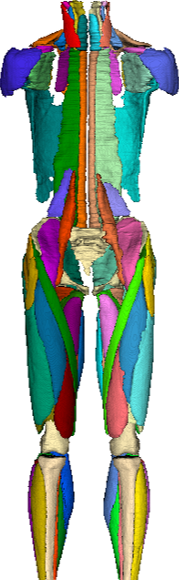

Whole-body muscle segmentation

Designed for whole-body and clinical imaging with consistent labelling across muscles and bones, enabling large-scale, multi-region analyses.